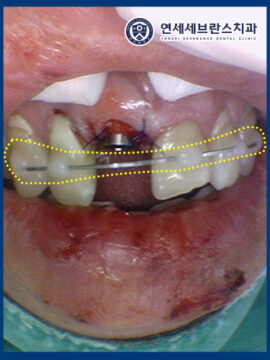

그리고 정출된 앞니를 재위치 시킨 후

스프린트를 이용해 고정까지 진행 후

마무리하였습니다.

또한 치아가 정출된 부위는

재위치 후, 앞니 6개 스프린트를 부착하여

4주간 고정하여 치료를

진행하기로 하였습니다.